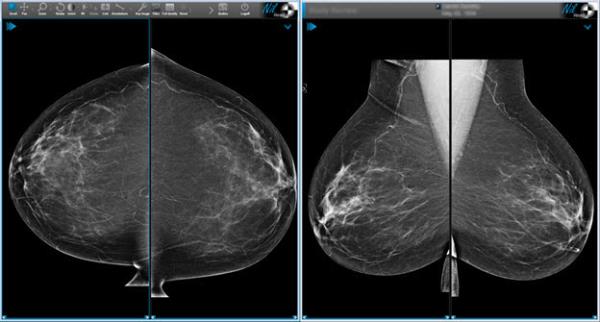

Sample layouts and views

The following examples show common ways to arrange images using study layouts and views. Available views depend on your NilRead implementation.

Multi-monitor auto-aligned mammography hanging protocol